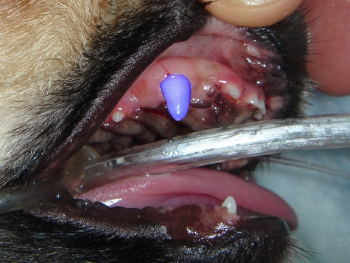

● 上顎乳歯犬歯が抜けなかったことによる不整咬合

乳歯犬歯が抜けなかったことにより、永久歯犬歯が前方に移動し(より鼻先の方向)下顎の犬歯により永久歯犬歯が外側に持ち上げられてしまっています。

緑:上顎永久歯犬歯。適正な場所よりも前方かつ外側にある

青:上顎乳歯犬歯。本来は抜けているべきであるが、抜けていないために、永久歯犬歯(緑)を異常な場所に圧迫している。

赤:下顎永久歯犬歯。正常な位置よりも内側かつ前方にずれている。また上顎の永久歯犬歯(緑)を下から押し上げている。